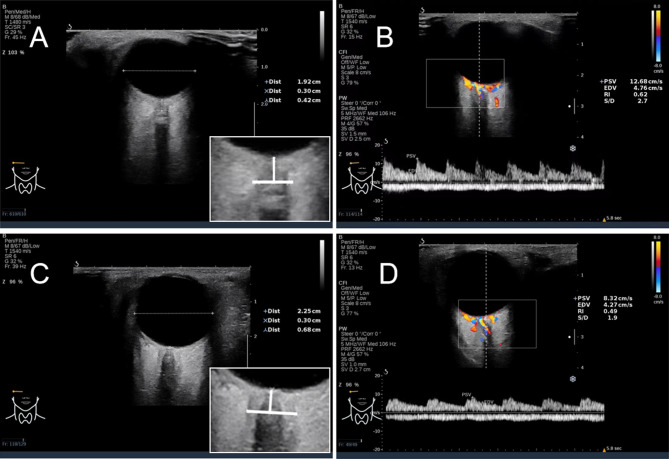

Methods: In this prospective diagnostic study, 136 neurology patients scheduled for lumbar puncture underwent pre-procedural ultrasound measurement of optic nerve sheath diameter (ONSD), ONSD-to-eyeball transverse diameter ratio (ONSD/ETD), and central retinal artery hemodynamics (peak systolic velocity [PSV], resistance index [RI]). Patients were classified as IICP (CSF pressure > 200 mmH₂O) or normal ICP (NICP) groups. Parameter performance was analyzed via ROC curves; multivariate logistic regression constructed a predictive model.

Results: The IICP group (n = 52) showed significantly higher ONSD (5.06 ± 0.49 vs. 4.19 ± 0.82 mm), ONSD/ETD (0.24 ± 0.02 vs.0.19 ± 0.04), and RI (0.66 ± 0.07vs.0.56 ± 0.09) but lower PSV (9.45 ± 1.38 vs.10.86 ± 2.14 cm/s) versus NICP (n = 84) (all P < 0.001). The integrated model (ONSD + ONSD/ETD + PSV + RI) achieved superior diagnostic accuracy: AUC 0.95 (95% CI: 0.922-0.988), sensitivity 88.1%, specificity 98.0%, Youden's index 0.86-significantly outperforming any single parameter (AUC 0.67-0.87, P < 0.001)-with the predictive equation: Logit(P) = 1.94×ONSD-84.6×ONSD/ETD + 0.79×PSV-3.8×RI + 11.05.